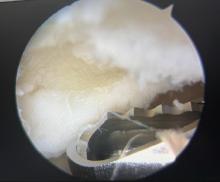

图1

关节镜下使用刨刀清理损伤软骨"